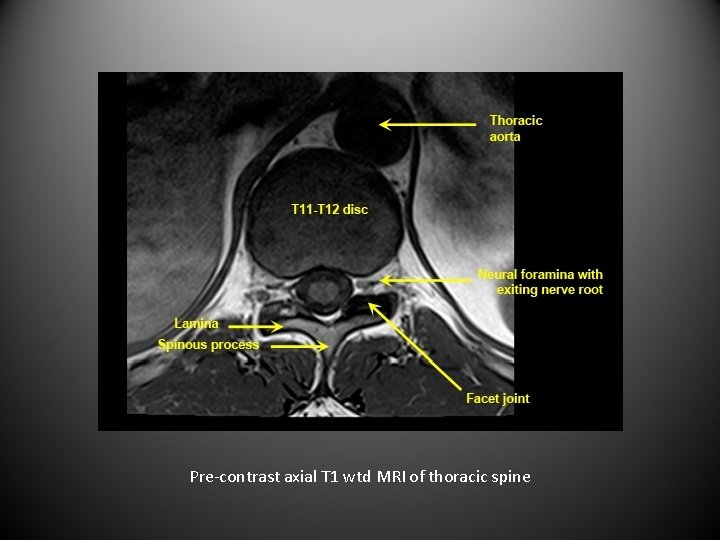

Pre-contrast axial T 1 wtd MRI of thoracic spine